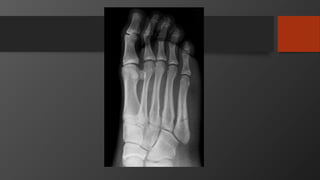

Fifth Metatarsal Fractures

• Common injury

• Divided into 3 zones

• Zone 2 is Jones fracture

• Zone 1 is Pseudojones fracture